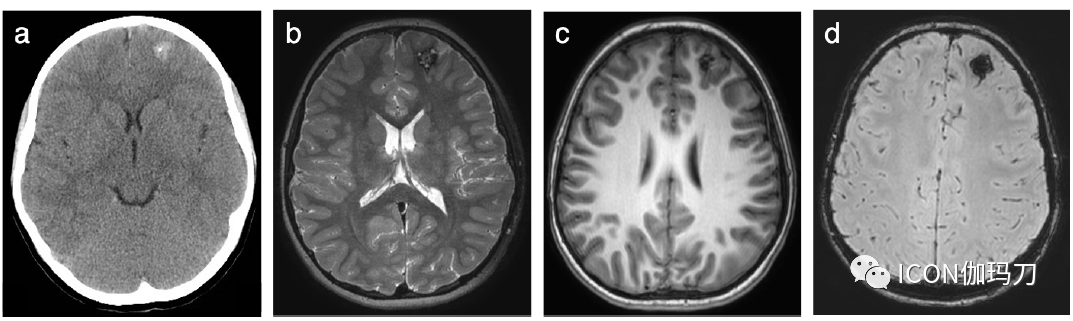

如上所述,CCMs的大小不一,从微小的点状病变到更大的可能是新发的巨大CCMs。虽然其临床、外科或组织病理学表现没有不同,但其放射影像学表现可能有显著差异。虽然许多CCMs在CT上通常难以识别,但较大的病灶更为明显,表现为复杂的、分叶状和超衰减(hyperattenuating)的肿块,后者继发于偏心和点状钙化(eccentric and punctate calcification),导致斑点状(speckled)表现。在MRI呈囊性表现主要是高(内在的)T1-WI信号强度(They appear cystic on MRI with spandominantly high (intrinsic) T1-WI signal intensity),但由于存在不同年龄的血液产物也有明显异构(图4)。在SWI上,较大的病变可能显示轻度病灶周围水肿和可能伴随着其他小的点状病变(图4)。可以忽略常规MRI序列,CT上可能是隐匿的。值得注意的是,微小的点状磁敏感伪影可能代表毛细血管扩张(capillary telangiectasia),这也是低流量病变,但潜伏期比CCMs预期的短,通常在低剂量辐射暴露后1-2年出现。

图3、所选轴位神经影像来自12岁男性,有左额CCM伴癫痫发作。(a)头部CT显示左侧额叶有偏心性钙化的高密度区域。(b) T2-WI和(c) T1-WI显示左额叶特征性小叶“爆米花”表现,信号强度不均,反映了血红蛋白破裂的不同阶段(高铁血红蛋白引起中央高信号,含铁血黄素沉积引起低信号边缘包围)。(d) SWI在同一位置显示显著的“开花”伪影,这是CCM的典型特征。靠近或累及大脑皮层的病灶可能是潜在的癫痫发作病灶(致癫痫灶)。对患者服用药物无法控制的癫痫灶进行显微外科切除,术后治愈。随访 MRI未发现残留病灶。